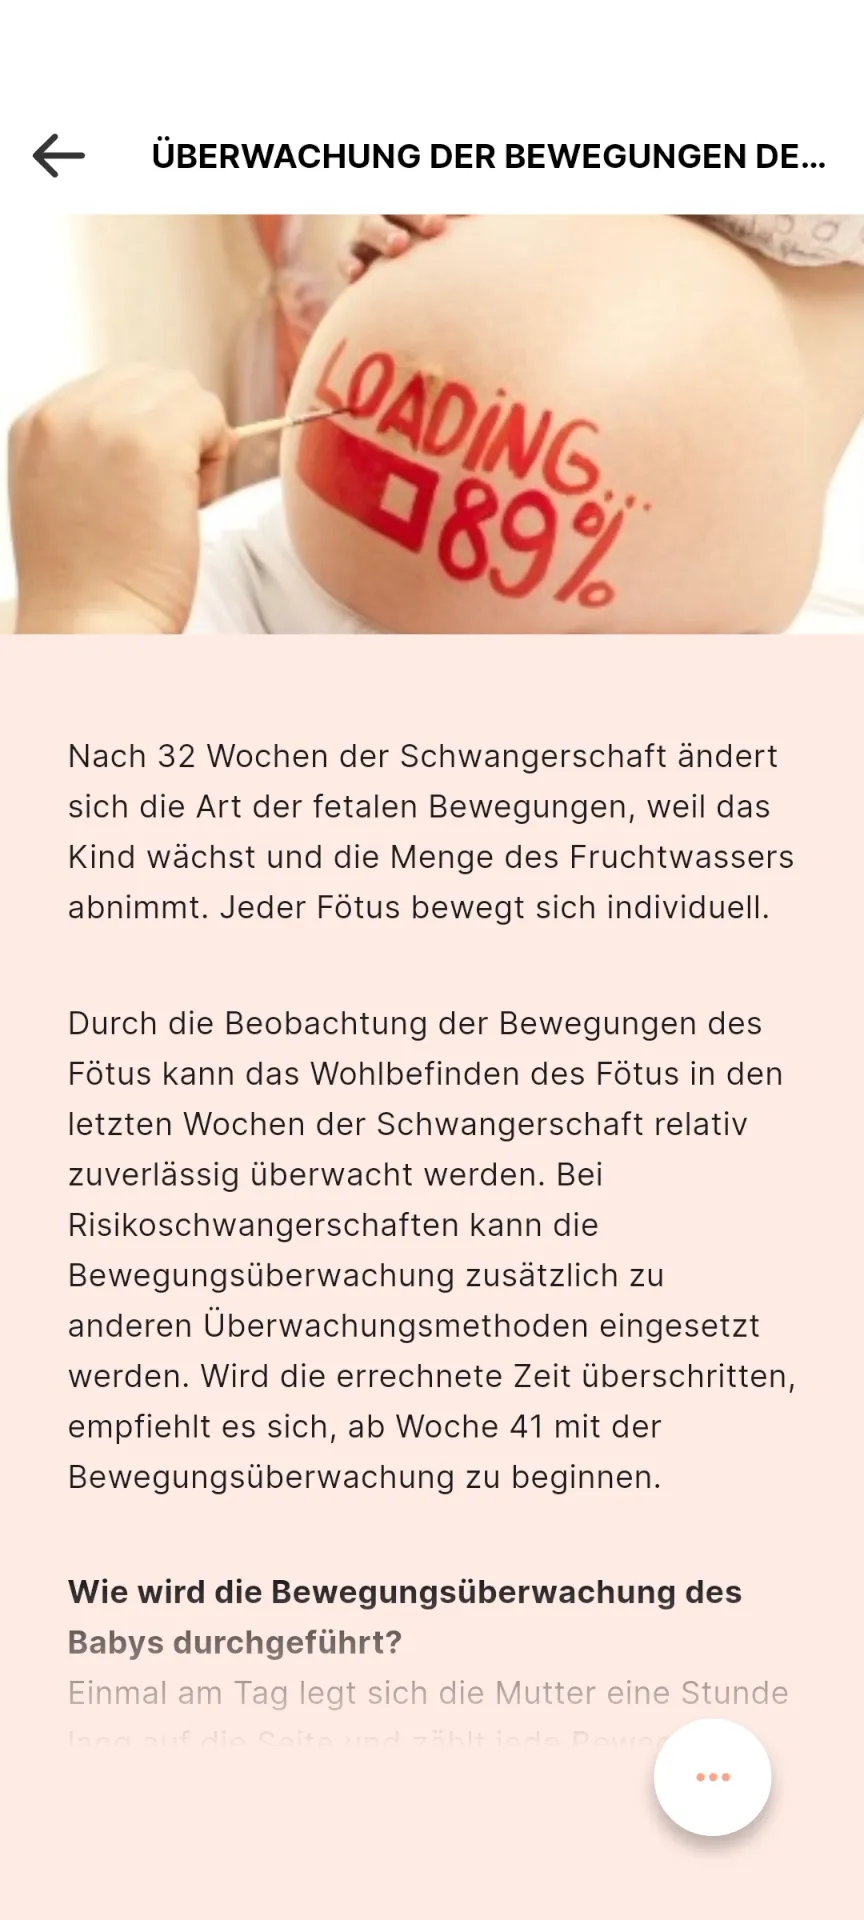

Your companion from pregnancy to early childhood

In the vulnerable phase of early parenthood, reliable information is crucial. The Neuvola app offers multilingual access to professionally verified content on pregnancy, childbirth, and baby care.

With the groundbreaking, non-generative chat function, families can safely and intuitively search for information about pregnancy, childbirth, and baby care.

Clinically verified information is available around the clock, automatically in 15 languages.

The information within the app is never generated during the usage, but carefully crafted with the healthcare professionals. There's no risk of hallucinating AI.